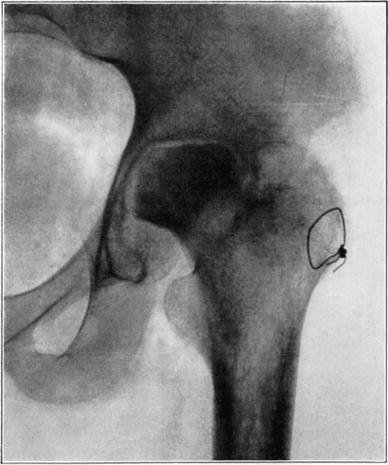

Death of the proximal fragment predisposes to non-union, but union occurs in a considerable percentage of the cases with a dead head in which there is impaction of fragments or in which there is efficient reduction and fixation of fragments, the best results apparently being obtained from the closed abduction method of Whitman. At the end of the period of immobilization the distal living fragment usually shows roentgen-ray signs of reduced density due to atrophy of disuse, but the necrotic head which cannot atrophy casts practically as even and heavy a shadow as at the time of fracture. This usually makes it possible to diagnose necrosis roentgenologically at this stage.

If bony union occurs the head is gradually invaded by the ingrowth of tissue from the distal fragment and sometimes from the hypertrophied round ligament. The necrotic marrow is replaced by vascular connective tissue and eventually by bone marrow, but the necrotic bone is much more slowly absorbed and replaced by a variable amount of irregularly arranged living bone. The necrotic cartilage is slowly absorbed and replaced by fibrous tissue, fibro-cartilage, and to some extent eventually by new hyaline cartilage. If too much weight is borne on the head before it has been transformed into new bone, its weight-bearing portion may collapse with a resultant deformity and a poor functional result, but this may be averted by prolonged avoidance of weight-bearing. The functional stimulation which comes from motion of the limb without weight-bearing is sufficient to hasten transformation of the head.

Necrotic femoral head casting heavier shadow than surrounding atrophied living bone.

Roentgenogram of slice of excised head in Fig. 7, showing old necrotic bony trabeculae still undisturbed.